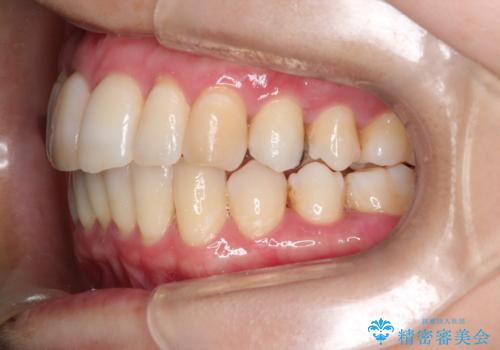

再矯正をインビザラインで目立たず手軽に

- 以前矯正をしていたが、わずかに後戻りをしてしまったのを主訴に来院されました。

装置はなるべくつけたくないとのことで、インビザラインにて治療することとなりました。

以前ワイヤー矯正をされていた方は、装置をつけての再矯正を希望されない方もいます。

その場合にインビザラインをお勧めさせていただいております。

後戻りがわずかな場合は、期間も短くて済む場合があります。